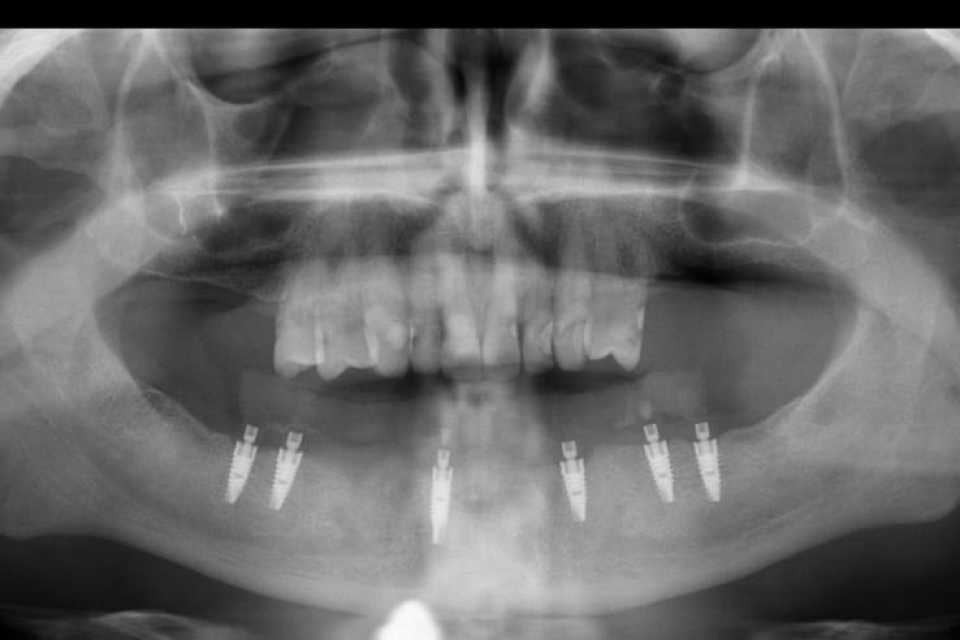

Pacientul Nicu D., în vârstă de 50 de ani, s-a prezentat în cabinet cu o edentație totală mandibulară în urma unei boli parodontale.

Împreună cu pacientul am hotărât realizarea unei lucrări protetice fixe inșurubabile pe 6 implanturi (implanturi Paltop). Lucrarea a fost realizată din ceramică pe zirconiu.